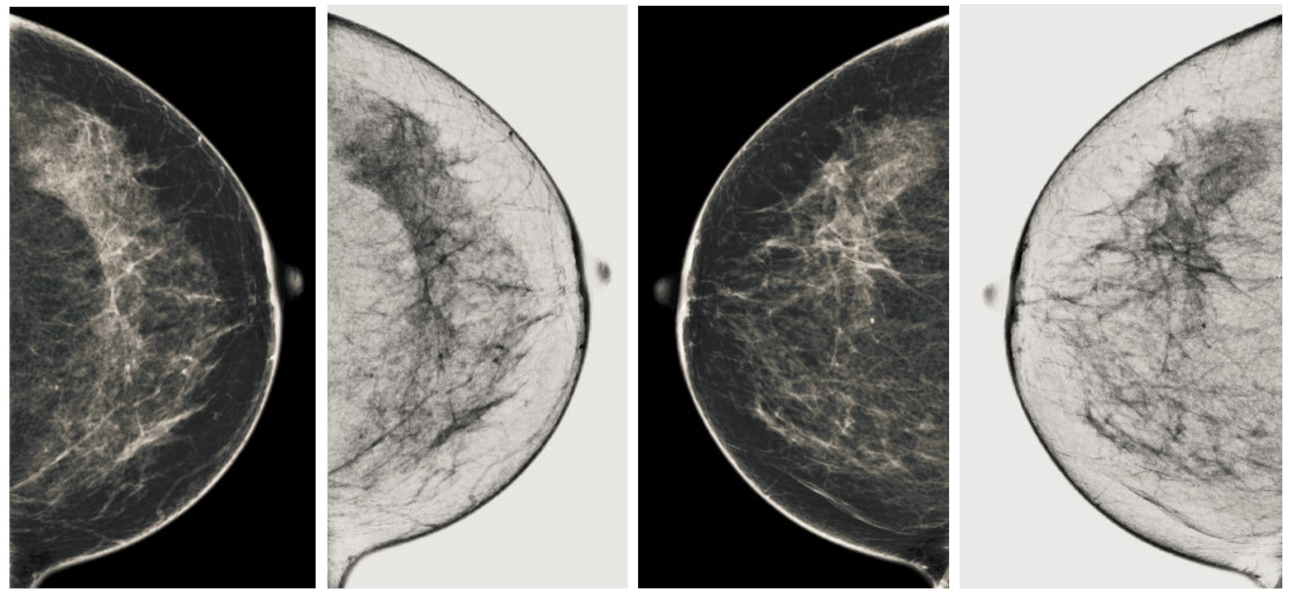

Figure 9.

Analysis of CC view of BI-RADS-2 mammogram images.

Figure 10.

Analysis of MLO view of BI-RADS-2 mammogram images.

We also measured the PSNR, the image contrast, and the EME of each category of databases, as we analyzed the image in terms of visual observation. The Table 3 shows the performance of our proposed image enhancement method. It can be seen from the Table 3 that our proposed method improved PSNR, contrast, and EME, and this also shows that our method can work on every category of BI-RADS. Because many techniques do not work on higher grade BI-RADS due to the complexity and the images are not of good quality. We obtained an average improvement in PSNR, contrast, and EME in the Table 4. For more observations, we analyzed the visual image of each category and we analyzed the CC and MLO of each category as shown in the Figure 7, Figure 8, Figure 9, Figure 10, Figure 11, Figure 12, Figure 13, Figure 14, Figure 15 and Figure 16. From the figures, every detail of image of every category can be observed, leading to better segmentation of the abnormal region. This image enhancement technique can be used as preprocessing steps for the detection of breast cancer. It is a very fast processing algorithm and it takes on 21.13 s. It gives opportunity to medical experts to analyze the mammogram images very quickly to propose the timely treatment.